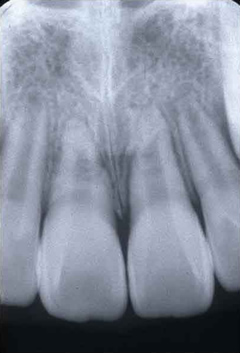

症例

写真は2本の歯の複雑な歯根破折と別の1本の挺出性脱臼(折れずに抜けている)、および、上あご真ん中で大きな歯槽骨骨折を起こした患者さんの治療前の写真です。

多くの損傷があり、処置はそれほど簡単ではないのですが、けがをした直後であったこと、受傷歯が幼若永久歯(歯根がまだ十分に完成していない)であったこと、処置が正確であったことから、抜歯も考えなければならないような歯が、神経も残すことができ、何事もなかったかのように治っています。